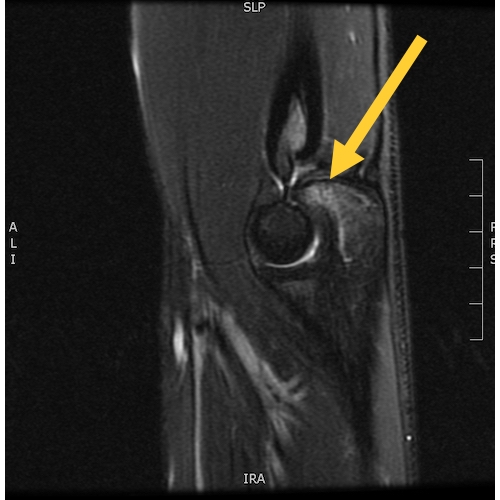

| Medial Elbow Pain In A Youth Baseball Pitcher: The Funny Bone Is Not So Humerus - Page #3 | |||